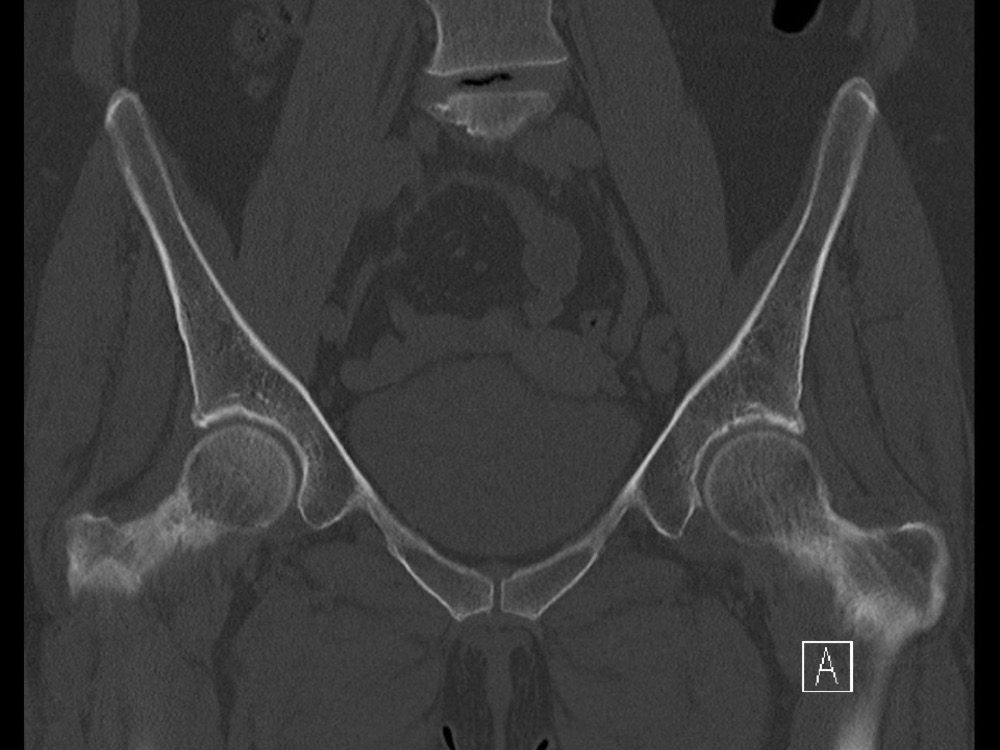

Douleurs de hanche

Linda Ouerd 06/11/2019